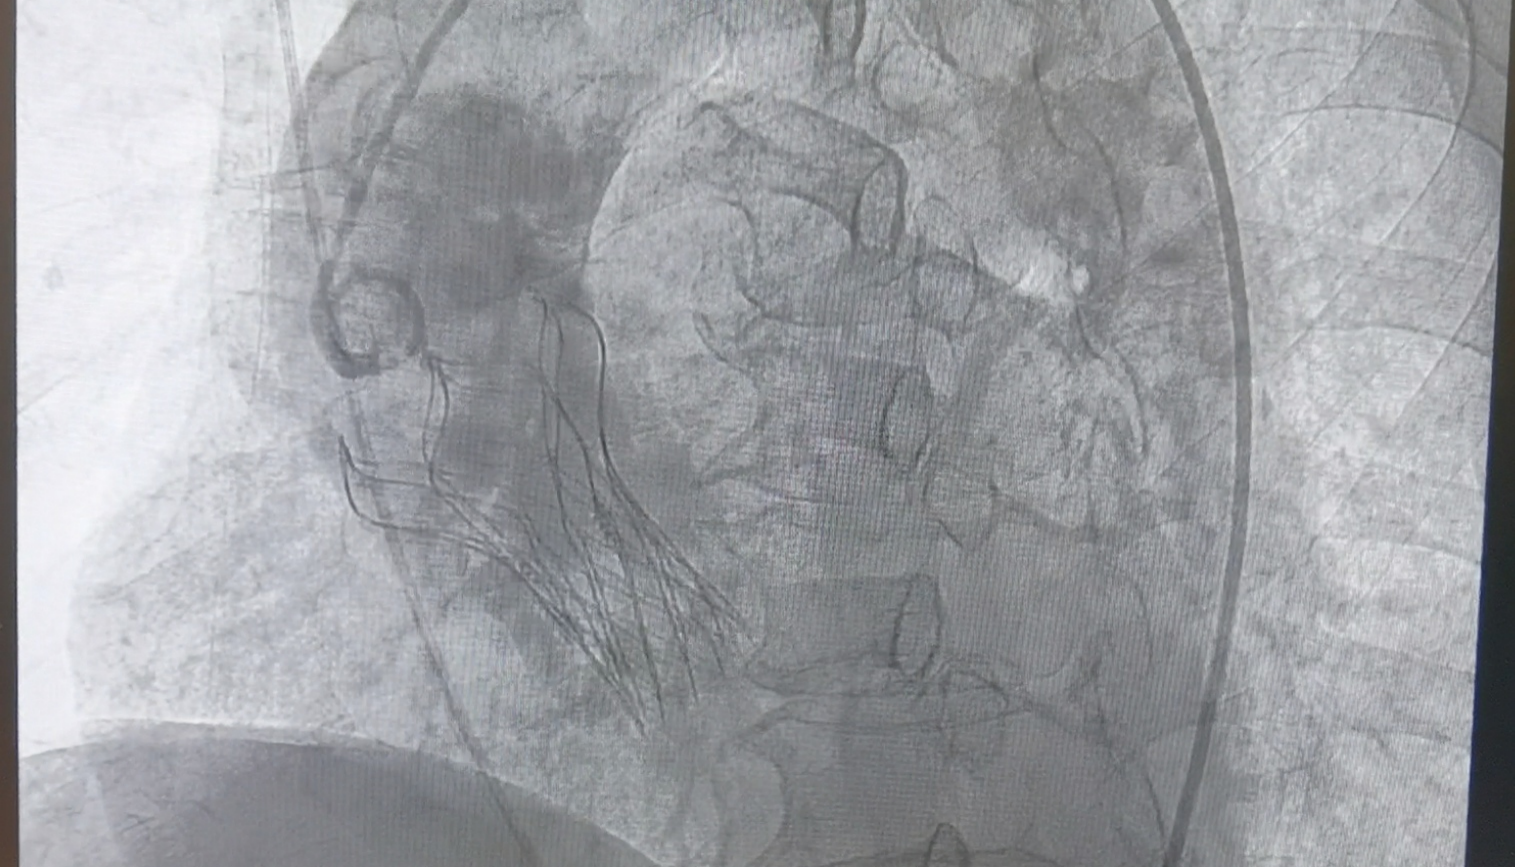

2025年10月27日,在南阳市中心医院东院区导管室里,正在进行着东院区的首例经导管主动脉瓣置换术(TAVR)手术。负责手术的是结构性心脏病病区杨侃教授,王登峰教授,范迪堃教授团队,接受手术的是一位73岁高龄主动脉瓣重度狭窄患者。监护仪屏幕上,绿色的波峰上下浮动,象征着心脏跳动的传出的滴滴声敲打在手术室每个人的心上。最后几秒,整个科室人员几乎屏住呼吸,眼睛紧紧盯着前方的瓣膜定位造影,空气仿佛凝固了一般,所有人都在等待着……瓣膜送达预定位置后,精准释放,立即开始工作。即刻造影及超声未见瓣周漏,主动脉瓣跨瓣压差正常,手术圆满结束!瞬间,手术室里的每个人都仿佛翻过了一座大山,如释重负!

10月27日,全员齐到位,在医院的大力支持及多学科的密切配合下,结构性心脏病病区杨侃教授,王登峰教授,范迪堃教授团队按照既定方案为老人实施手术,通过老人股动脉植入瓣膜,瓣膜输送、定位及释放......整个手术过程一气呵成。

手术后,即刻造影及超声提示未见反流,无瓣周漏,瓣膜植入位置良好,即刻超声提示主动脉瓣跨瓣基本无压差,未出现相关并发症,手术圆满成功。